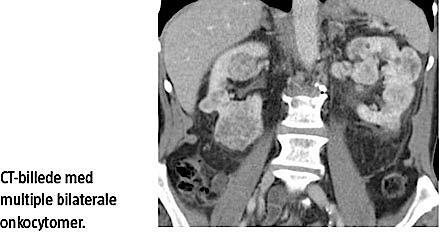

En 77-årig mand blev undersøgt på grund af stigende kreatininniveau og faldende glomerular filtrationsrate. Han havde ingen urinvejssymptomer. En UL-skanning af nyrerne viste multiple, heterogene solide tumorer bilateralt. En CT viste multiple, veldefinerede tumorer, hvoraf de større havde central hypoattenuering. Der blev foretaget bilateral nyrebiopsi, og malignitet kunne ikke udelukkes. Herefter blev der udført højresidig nefrektomi, efter at en renografi havde vist, at højre nyre varetog 42% af den samlede nyrefunktion. Nyren målte 12,5 × 7 × 4 cm og indeholdt talrige, op til 4 cm store gyldentbrune tumorer. Den histologiske undersøgelse, der omfattede immunhistokemi, sandsynliggjorde, at der var tale om et onkocytom og ikke et kromofobt karcinom. Ved elektronmikroskopering (EM) bekræftedes diagnosen. Der var postoperativt et godt forløb, bortset fra en stigning i kreatininniveauet fra 120 til 180 mikromol/l.

Onkocytomer kan påvises med flere radiologiske metoder. Med UL-skanning kan man finde hypo-,

iso- og hyperekkoiske tumorer. Centralt udstrålende blodkar kan identificeres med farve–Doppler-UL [4]. Med CT ses en velafgrænset, homogen og hypervaskulær nodulus. Homogeniteten brydes centralt i onkocytomet, når det har et centralt ar [5]. Med MR-skanning ses onkocytomer som en velafgrænset homogen masse, der er iso- eller hypointense sammenlignet med den omkringliggende cortex. En centralt udstrålende struktur kan ses i store noduli [5].